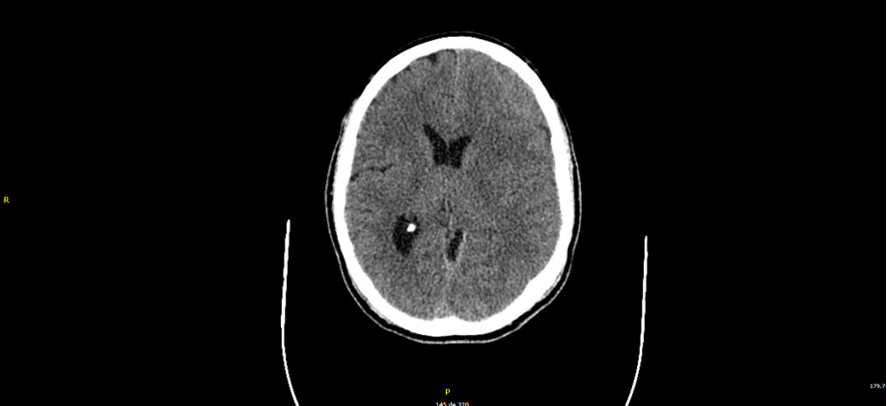

• TAC de cráneo: Hematoma subdural frontoparietal izdo, de probable evolución subaguda. Efecto de masa sobre parénquima cerebral, con obliteración de surcos de la convexidad izda, con mínimo desplazamiento de línea media (3 mm).

• Hematoma subdural frontoparietal izquierdo subagudo postraumático

Persiste colección hemática con puntos de resangrado. El paciente persiste pauci/asintomatico se plantea puede beneficiarse de embolización de meningea media.